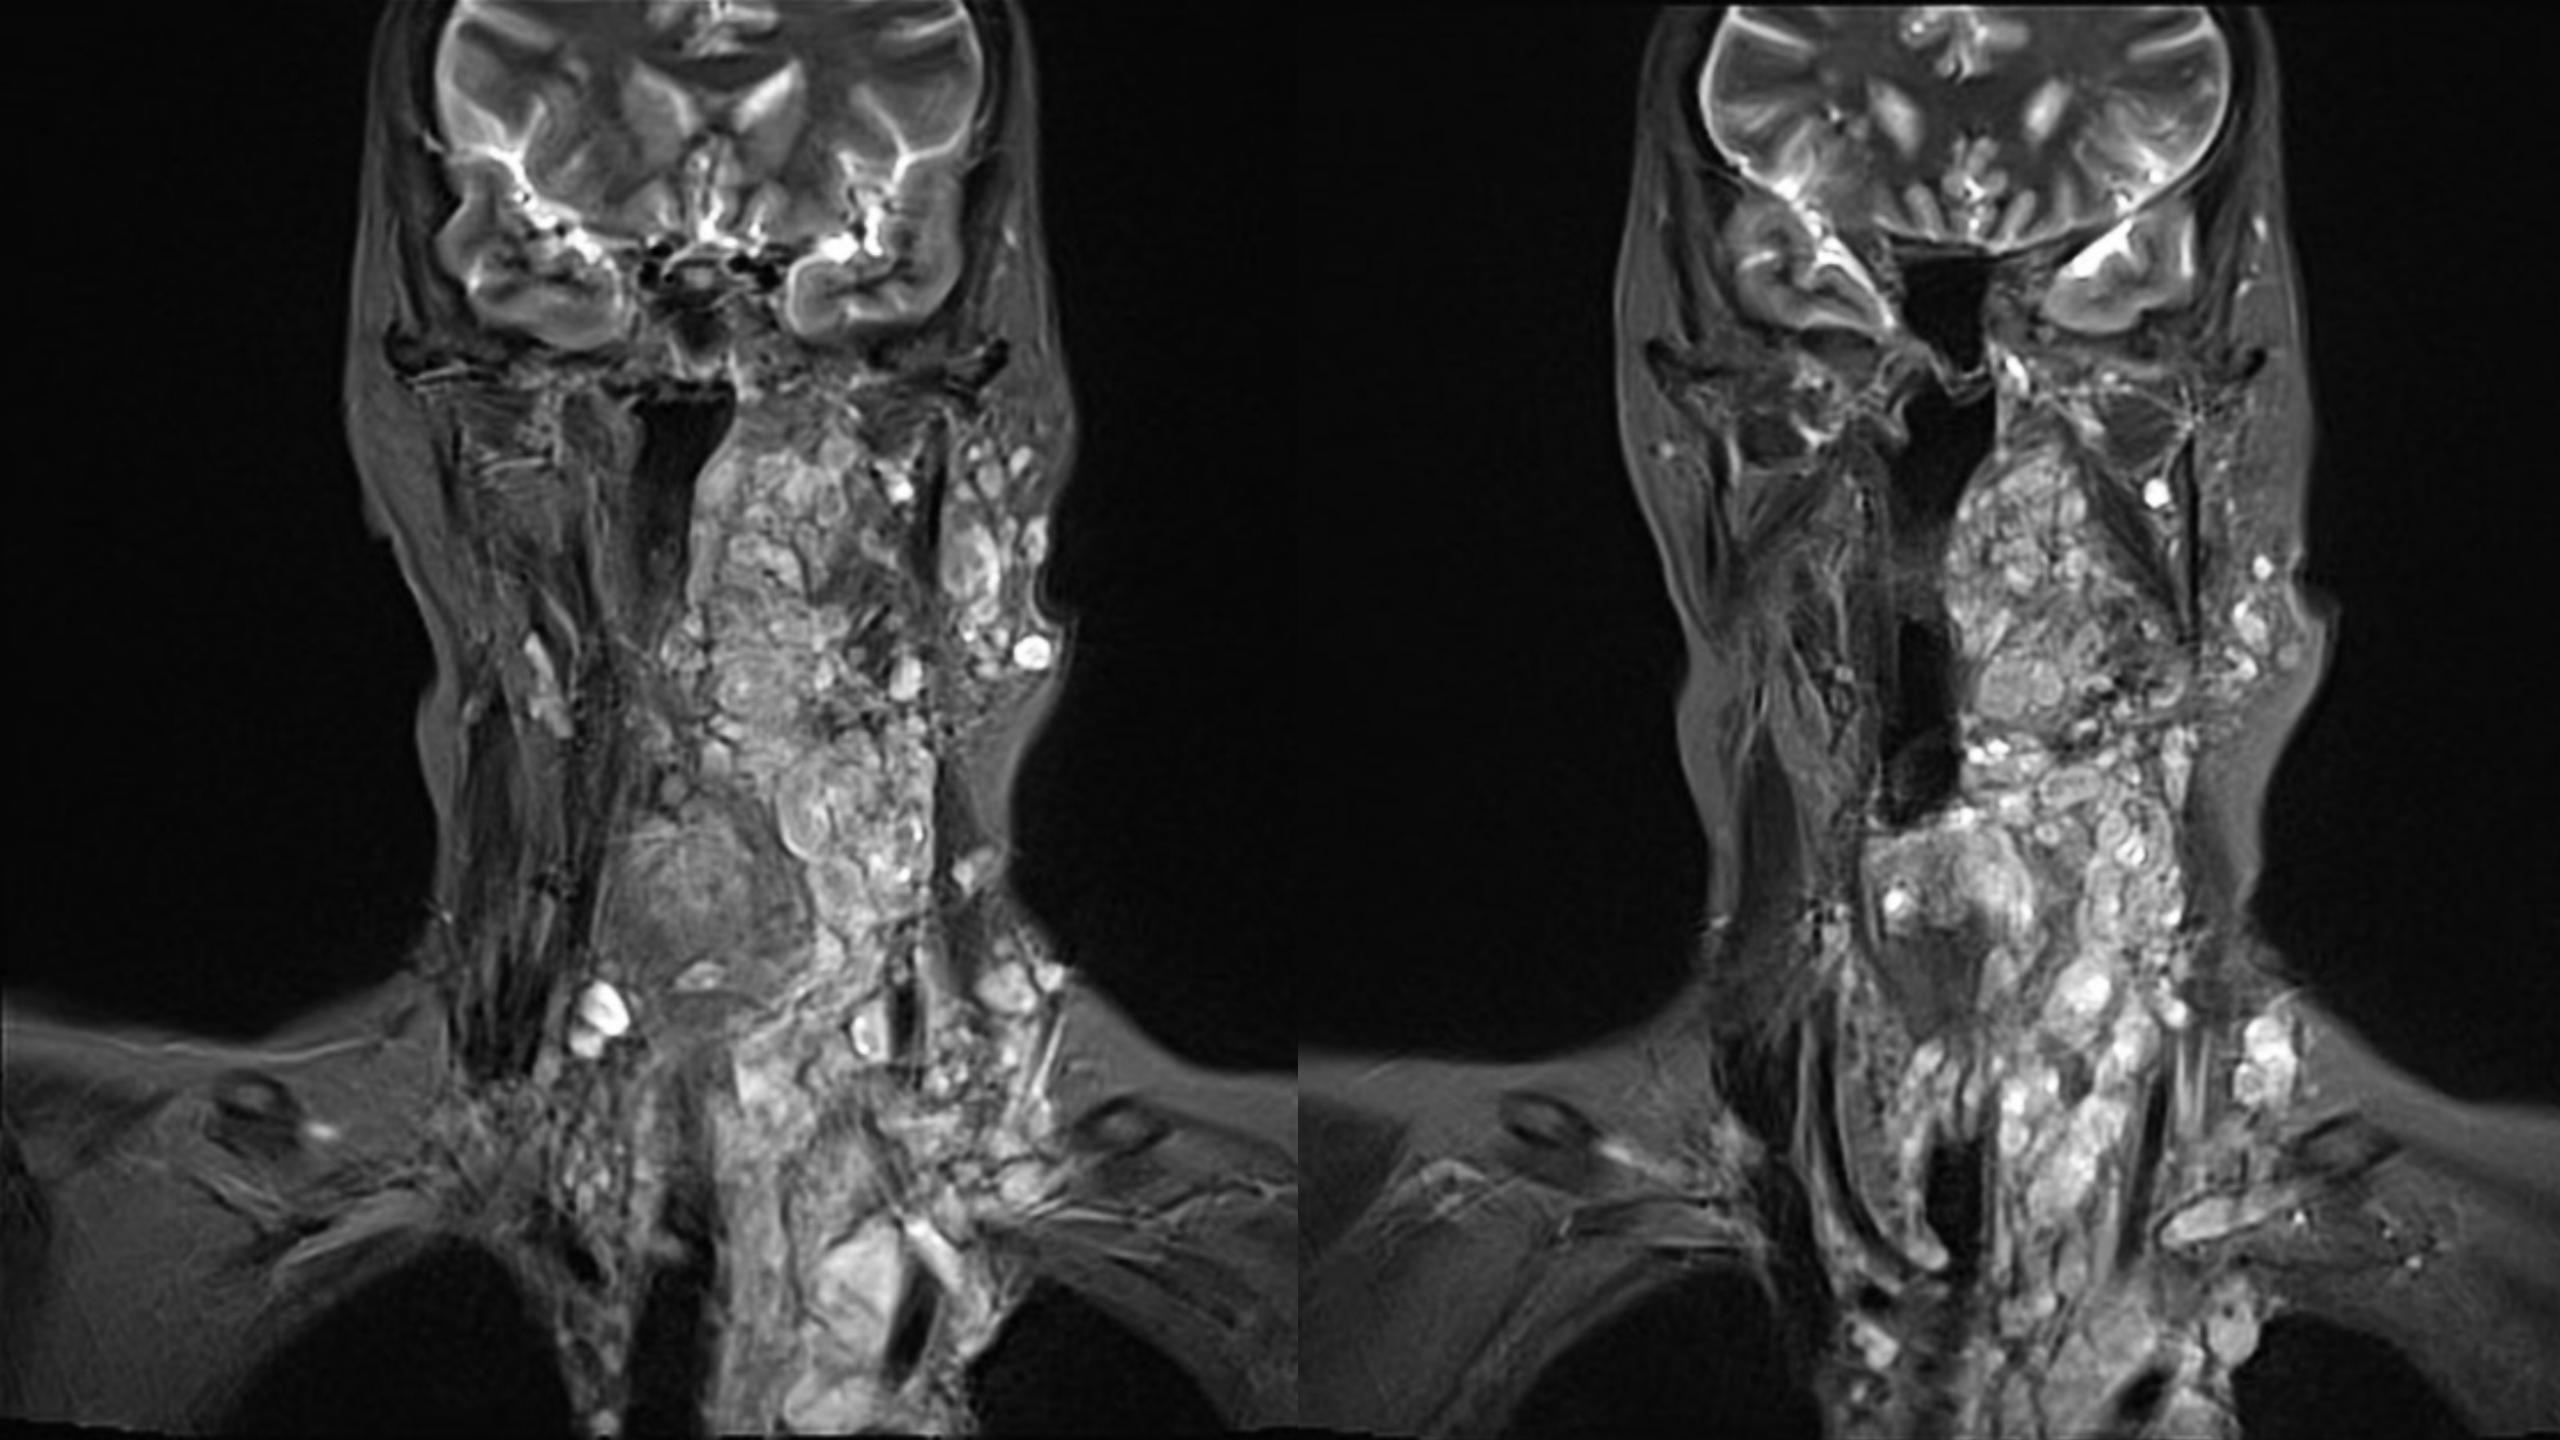

神经纤维瘤病(NF1)